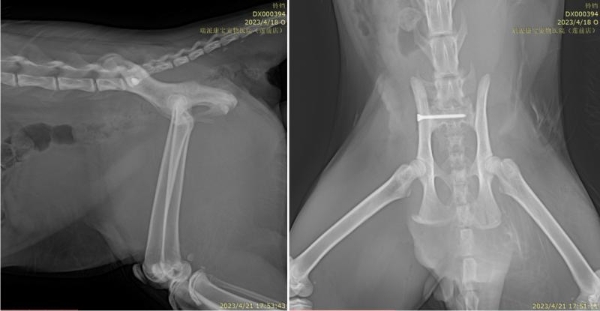

一只2岁7个月的雄性英国短毛猫,从8楼高处坠落,出现尿血、呼吸急促及右前肢与骨盆区严重功能障碍。接诊后,吴泉太院长立即启动多系统评估。X线检查显示右侧肱骨远端粉碎性骨折、髋关节脱位伴髂骨前移;血液检测提示高血糖、肾功能异常及红细胞增多,综合确诊为“高坠综合征伴多发性骨折与脏器损伤”。

面对这一危及生命的复杂创伤,吴院长制定了分期治疗方案:优先稳定生命体征,通过静脉补液纠正脱水与电解质紊乱,同时实施强效镇痛与抗生素预防感染。待患猫状况稳定后,随即开展骨科重建手术——包括右侧肱骨骨折内固定术、髋关节复位与髂骨稳定术,精准恢复骨骼结构与关节对位。

术后3周复查显示,骨折部位愈合良好,关节功能逐步恢复,血液指标恢复正常,精神与食欲明显改善。这也充分体现了吴泉太院长拥有在严重创伤救治中的综合决策能力,既能通过精准的骨科技术重建骨骼结构,又能依托全面的内科管理为复杂创伤患者创造最佳康复条件。